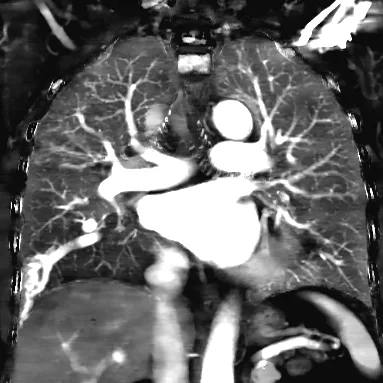

66 year old female with long-standing polycythemia, found to be hypoxemic on exam (O2 sat 93% on room air). Chest X-ray shows persistent right lung "infiltrates", so a chest CT was performed. There is a history of AV malformations in the brain and colon.

Routine chest CT is straightforward: a large complex AV malformation is seen in the right lower lobe. Feeding artery is 8 mm. There are probable additional multiple tiny AVM's in the lungs. Patient most likely has Osler-Weber-Rendu or hereditary hemorrhagic telangiectasia.

Iodine map in the coronal plane nicely illustrates the pulmonary AVM and adjacent perfusion defect. This is because of blood (and iodine) shunting into the low pressure system, and results clinically in hypoxemia, that then sets off compensatory mec…

Iodine map in the coronal plane nicely illustrates the pulmonary AVM and adjacent perfusion defect. This is because of blood (and iodine) shunting into the low pressure system, and results clinically in hypoxemia, that then sets off compensatory mechanisms resulting in polycythemia.